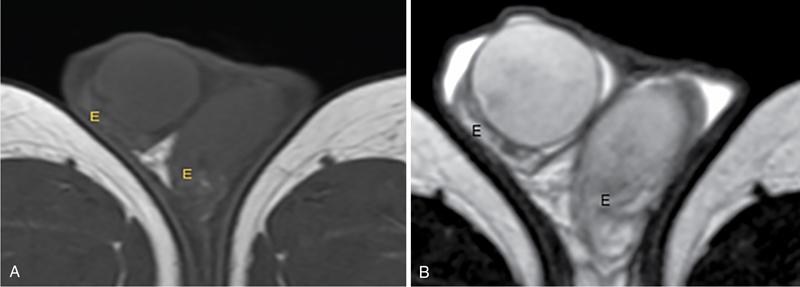

IMAGING ANATOMY OF MALE REPRODUCTIVE SYSTEM Ganesh Rajagopal The male reproductive system is formed by testes, ejaculatory ducts, seminal vesicles (SVs), prostate and penis. Various diagnostic imaging modalities like ultrasound (US), computed tomography (CT), magnetic resonance imaging (MRI) and positron emission tomography (PET) are helpful in the diagnostic evaluation of male reproductive system. Various indications for imaging may include acute scrotum (testicular torsion, trauma and epididymo-orchitis), scrotal swelling (hydrocele, spermatocele, idiopathic scrotal wall oedema and scrotal abscess) and infertility. US and MRI are the commonly used imaging modalities in male reproductive system which complement each other. CT is not very useful due to poor contrast resolution. Ultrasound imaging (US) with a high-frequency linear (7.5–10 MHz) transducer probe has become the imaging modality of choice for scrotal evaluation. Scrotal US is an excellent imaging modality as it can demonstrate abnormalities in testis as well as in paratesticular structures. Scrotal wall is formed by the skin, superficial fascia, dartos muscle, the external spermatic fascia, cremasteric fascia and the internal spermatic fascia. The scrotum is divided into two cavities by a median raphe. This multilayered scrotal wall is poorly delineated in US and MRI, it is typically hypointense on both T1- and T2-weighted images. Testes are paired organs, located normally in scrotal sac, suspended by the spermatic cords. Each testis is examined in orthogonal transverse and longitudinal planes, with both grey scale and colour Doppler modes, to assess its volume and blood flow. Volume of testis is calculated by length × height × width × 0.71. A total volume (both testes) of >30 mL and a single testicular volume of 12–15 mL is generally considered normal for adults. Testes are supplied by the testicular arteries, which arise from the aorta and enter the spermatic cord at deep inguinal ring to reach the upper pole of testis. Pampiniform plexus of veins surrounds the testis and appears as a serpiginous tubular structure posterior to it, measuring >2–3 mm in diameter. Testes are oval shaped, with homogeneous echotexture on grey scale US. Along with the epididymis, they are surrounded by an echogenic capsule, known as the tunica albuginea. Tunica albuginea is covered by tunica vaginalis, which is a remnant of the processus vaginalis and both represent closed sac of peritoneum with two layers. This tunica albuginea is seen extending into posteromedial testis and form the mediastinum testis (Fig. 11.2.1.1), which consists of ducts, nerves and blood vessels. The mediastinum testis is seen as a thin echogenic band. Rete testis is formed by the convergence of seminiferous tubules, seen as a hypoechoic area adjacent to mediastinum testes. The epididymis is a comma-shaped, elongated structure placed at the posterior border of the testis, which drains the efferent ductules (Fig. 11.2.1.2). It has head, body and tail. The head overlies the superior pole of the testis and is isoechoic or slightly hyperechoic whereas, the body and tail are located behind and along the inferior pole and are usually isoechoic. The tail of the epididymis continues into vas deferens (VD), which along with the nerves, lymphatic and vascular structures, forms the spermatic cord (Fig. 11.2.1.3). The spermatic cord appears as an echogenic band in the inguinal canal. The normal adult testis is a homogeneous oval structure that appears hyperintense on T2-weighted sequences and hypointense–isointense on T1-weighted images (Fig. 11.2.1.4). The tunica which surrounds the testis is hypointense T1- and T2-weighted sequences. Epididymis is isointense on T1-weighted images but hypointense on T2-weighted images compared to testis (Fig. 11.2.1.5). Both testicles and epididymis enhance after intravenous administration of gadolinium (Gd) MR contrast agents. Prostate, though visualized by transabdominal scan is better assessed by transrectal high frequency (7.5–10 MHz) ultrasound transducer (TRUS) with patient in left lateral decubitus position. The prostate gland is divided into the anterior fibromuscular stroma (devoid of glandular tissue), transition zone, central zone, periurethral zone and peripheral zone. The base of the prostate is located superiorly and contiguous with the bladder neck whereas, the apex of the prostate is located at the inferior aspect continuous with the striated muscles of the urethral sphincter. The neurovascular bundle is seen to course near the posterolateral aspect of prostate, which is a preferential route of tumour spread. The prostate appears as a cone-shaped organ and shows uniform low echogenicity (Fig. 11.2.1.6). The outer gland (central and peripheral zones) is generally more echogenic than the inner gland. The transition and central zones of the prostate have similar MR signal intensity and cannot be differentiated, hence, are collectively referred as the central gland. On T2-weighted MR images, the normal peripheral zone is homogeneously hyperintense, whereas the central gland tissue is typically hypointense or isointense compared to the skeletal muscle (Fig. 11.2.1.7). The capsule and the anterior fibromuscular stroma appear hypointense on T2-weighted MR images. The SVs are seen as septate tubular cystic structures, appearing uniformly anechoic in US, above the prostate with distal portion of VD is seen medial to it. The duct of SV and VD joins to form the ejaculatory duct, which drains into the prostatic urethra via verumontanum. SVs show ‘bow-tie’ appearance in transversal scans, and a club or tennis-racket shape in longitudinal scans (Fig. 11.2.1.8). On MR, SVs are seen as elongated fluid-containing structures with thin septa, which is hypointense on T1 and hyperintense on T2-weighted MR images (Fig. 11.2.1.9). The VD is seen as a tubular structure with low signal intensity in both T1- and T2-weighted images, on either side. The dilated distal portion of VD (ampulla), appears hyperintense on T2-weighted images, similar to that of the SV due to the fluid content (Fig. 11.2.1.10). The penis, being a superficial organ, is usually examined with US, although MRI is reserved as problem solving modality. The penile body contains two paired muscles – corpora cavernosa and a corpus spongiosum. The former performs as a main erectile body while the latter contains the penile urethra (Fig. 11.2.1.11). Dartos fascia forms the outer layer and the Buck fascia forms the inner layer, which contain the deep dorsal vein (DDV) and a paired dorsal neurovascular bundle. The corpus spongiosum and corpora cavernosa are of high signal intensities on T2-weighted MR images and intermediate-low signals on T1-weighted MR images. The tunica albuginea being a fibrous sheath, surrounds all the three muscles, is hypointense on all sequences (Fig. 11.2.1.12). IMAGING ANATOMY OF FEMALE REPRODUCTIVE SYSTEM Saranya The female reproductive system comprises of uterus, cervix, fallopian tubes, ovaries, vagina and vulva. Ultrasonography (transabdominal and transvaginal) is the primary imaging modality of choice for imaging the female pelvis. Computed tomography (CT) is less often used for pelvic imaging. It provides a quick and systematic overview with coverage of the abdomen in the same session. Hence, CT is well suited for staging pelvic cancers and for imaging gynaecologic and nongynaecologic diseases presenting with acute abdominal pain. Pelvic anatomy is well demonstrated by magnetic resonance imaging (MRI). The contrast resolution of T2-weighted images form the basis for superb tissue characterization of MRI. Uterus is a thick-walled fibromuscular organ composed of myometrium and endometrium. It has two major divisions, namely, the body (corpus) and cervix. The fundus lies above the ostia of fallopian tubes. The normal uterus measures between 5 and 9 cm in length and is in an anteverted position, in relation to the urinary bladder. The myometrium shows three layers on USG, a compacted thin, hypoechoic inner layer forms subendometrial halo, a thicker, homogenously echogenic middle layer and a thinner, hypoechoic outer layer (peripheral to arcuate vessels). The appearance of the endometrium varies with the phase of the menstrual cycle. It appears as a thin echogenic line early in the proliferative phase and shows hypoechoic thickening (4–8 mm) as proliferative phase progresses. It shows a triple layer (sandwich or trilaminar) appearance in the mid cycle and may measure up to 12–16 mm. During secretory phase after ovulation, the layers are seen hyperechoic due to the increasing complexity of glandular structure and secretions (Fig. 11.2.2.1). Postmenopausally, the endometrium decreases in thickness. Endometrial thickness of 5 mm is taken as cut-off. Women on hormonal therapy acceptable endometrial thickness is up to 8 mm. Three-dimensional US permits multiple views to be reconstructed from a single sweep through the uterus. Sonohysterogram is the study of choice for detailed evaluation of the endometrial cavity pathologies. The cervix begins at the inferior narrowing of the uterus (isthmus) at the internal os, which is identified by the entrance of uterine vessels. It has supravaginal and vaginal portions. It is 3–4 cm long and shortens after childbirth. In premenarche women, cervix is larger than corpus, forming approximately 2/3 of the uterine mass. During menarche, there is preferential growth of the corpus and in nulliparous women, corpus and cervix are roughly equal, whereas in parous woman, corpus forms approximately 2/3 of the uterine mass. Uterus is an extraperitoneal organ. The peritoneum extends over urinary bladder dome to anterior uterus, forming anterior cul-de-sac (vesicouterine pouch) and posteriorly, the peritoneum extends more inferiorly to the upper portion of vagina, forming the posterior cul-de-sac (pouch of Douglas, rectouterine pouch), which forms the most dependent portion of the female pelvis. Supporting ligaments of the uterus comprise mainly of broad ligaments, which extend laterally to the pelvic wall and round ligaments, which arise from uterine cornu near fallopian tubes to course anteriorly, pass through the inguinal canal to insert on the labia majora. Connective tissue thickening at the base of the broad ligament forms the uterosacral ligaments posteriorly, cardinal ligaments laterally and vesicouterine ligaments anteriorly. CT examination displays the uterus as a triangular or ovoid soft tissue structure behind the urinary bladder (Fig. 11.2.2.2). Following the administration of intravenous contrast, there is enhancement of myometrium that helps to delineate the endometrium. The vagina, cervix and corpus can be differentiated by morphological characteristics and enhancement pattern. The uterine corpus is typically triangular, whereas cervix is more rounded. The vagina has an appearance of flat rectangle at the level of fornix. The broad ligament and round ligaments are seen coursing laterally and anteriorly, respectively. The main source of vascular supply to uterus is from the uterine arteries. The uterine arteries pass within the broad ligament to enter the uterus, adjacent to the lateral fornices. The uterine artery passes over the ureter at the level of the cervix. Then it courses superiorly, along the lateral margin of the uterus and anastomoses with the ovarian artery. Uterine arteries give rise to arcuate arteries, which run in the outer third of myometrium. Radial arteries extend through the myometrium, which terminate as spiral arteries in the endometrium. The venous system parallels the arterial system, forms a complex venous network in the parametrium and drains to the iliac veins. Middle and lower thirds of the uterus are drained by obturator, parametrial and paracervical lymph nodes. Lymphatic drainage from the upper corpus and fundus goes to the common iliac and paraaortic lymph nodes. MRI provides a more comprehensive view of the uterine anatomy. On MRI, the uterus and cervix show uniform low to intermediate signal on T1-weighted images. On T2-weighted images, uterus shows three distinct zones, namely high signal endometrium, low signal junctional zone and intermediate signal myometrium (Fig. 11.2.2.3). The normal thickness of the junctional zone varies from 2 to 8 mm. A thickness of 9 to 12 mm is equivocal and greater than 12 mm is abnormal. Both endometrium and junctional zone become thin with oral contraceptive intake. Endometrial atrophies and the junctional zone is absent in postmenopausal women. The endocervical canal shows high signal on T2-weighted images, whereas cervical stroma shows low signal, contiguous with the junctional zone. An outer layer of intermediate signal smooth muscle is present. Nabothian cysts representing obstructed, mucous secreting glands are commonly seen as low signal on T1-weighted images and high signal on T2-weighted images. Parametrium shows low to intermediate signal intensity on T1-weighted images and variable signal intensity on T2-weighted images. The round ligaments and uterosacral ligaments show low signal intensity, cardinal ligaments and associated venous plexuses show high signal intensity on T2-weighted images. Ovaries are located posterolateral to the body of the uterus between the uterus and the pelvic sidewall. The internal iliac vessels lie immediately posterior to the ovary. Exact position is variable due to the laxity in the ligaments, parity, uterine size and position. On USG, medulla of the ovaries is mildly hyperechoic compared to the hypoechoic cortex. Developing follicles appear anechoic (Fig. 11.2.2.4). Corpus luteum may have a thick, echogenic ring and haemorrhage is common.